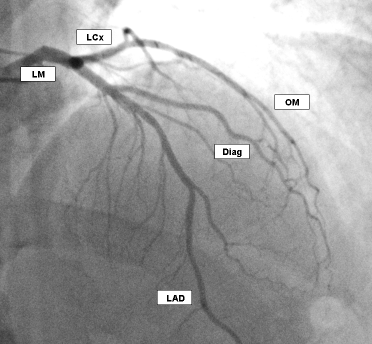

Where is the left coronary artery (LCA), and what part of the heart does it supply?

4

Left atrium and ventricle, 2/3 of septum

Which 2 vessels does the LCA bifurcate into?

Left anterior descending artery (runs down front of left heart)

Left circumflex artery (wraps around back of heart)

Where is the left anterior descending artery (LAD), and what part of the heart does it supply?

3

Anterior left heart, septum, apex, bundle branches

Where is the left circumflex artery, and what part of the heart does it supply?

2

Lateral and posterior left heart

Which coronary artery is seen with a CT angiogram in the LAO caudal view?

A

LCA and its bifurcation into the left anterior descending (LAD) and circumflex (LCX) arteries